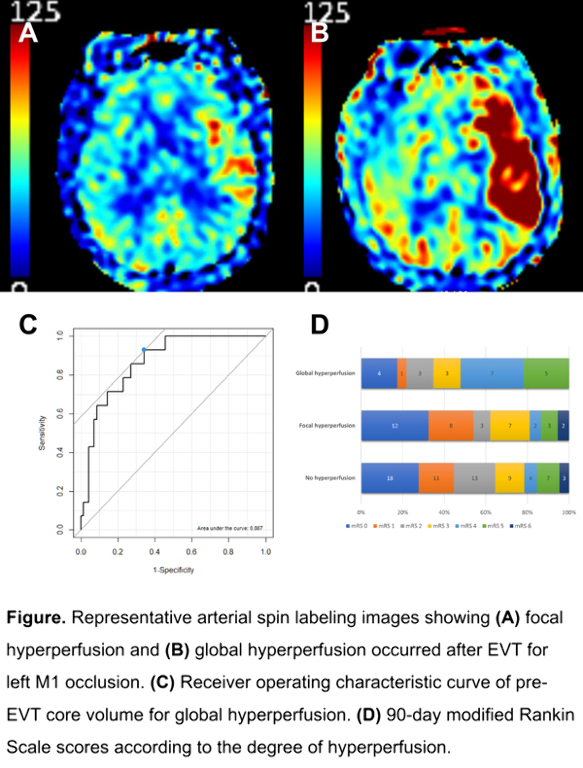

Patients with stroke may sometimes develop hyperperfusion after successful endovascular treatment (EVT). It is yet to be elucidated which factors affect post-EVT hyperperfusion and how hyperperfusion is associated with clinical outcome.

Consecutive patients who underwent EVT for anterior circulation occlusion and achieved successful recanalization (modified treatment in cerebral ischemia 2b–3) were reviewed. Hyperperfusion was categorized as follows based on post-EVT arterial spin labeling MRI: global hyperperfusion, increased cerebral blood flow (CBF) in ≥50% of previously occluded territory; focal hyperperfusion, increased CBF in <50% of previously occluded territory; and no hyperperfusion, no visible CBF increase. Factors associated with hyperperfusion were assessed and clinical outcome was compared among the hyperperfusion categories.

Among 125 eligible patients, 23 and 37 patients developed global and focal hyperperfusion, respectively. Compared with patients without hyperperfusion (n=65), global hyperperfusion group had worse neurologic severity and larger pre-EVT core. No significant difference was found between focal and no hyperperfusion groups. Pre-EVT core volume predicted global hyperperfusion with 92.9% sensitivity and 65.7% specificity (area under receiver operating characteristic curve, 0.867; 95% CI, 0.779–0.956). Global hyperperfusion group had worse 90-day outcome compared with focal hyperperfusion (modified Rankin Scale 0–2, 34.8% vs. 62.2%, p=0.072), and no hyperperfusion (34.8% vs. 64.6%, p=0.025) groups. Hemorrhagic transformation occurred similarly in the three groups.

Global hyperperfusion was associated with worse clinical outcome and tended to occur in patients with larger pre-EVT core. Future research is warranted to determine whether intervention such as blood pressure lowering improves outcomes in patients with global hyperperfusion.